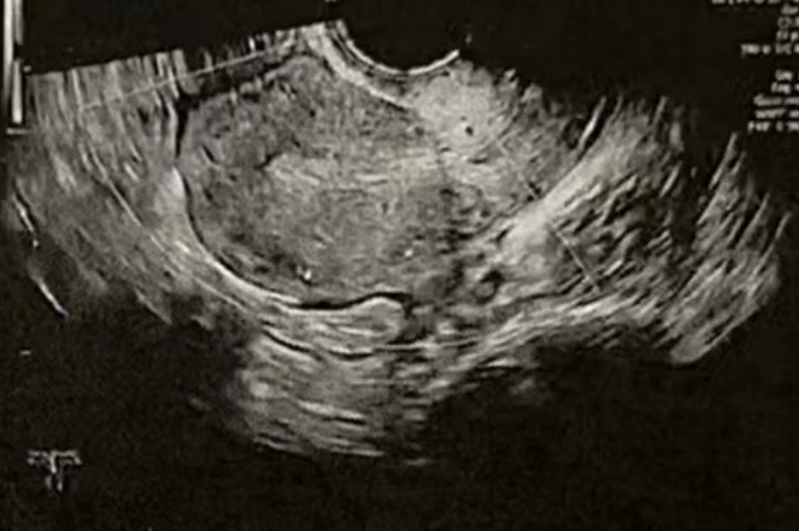

子宫内膜厚度:8.9 毫米

微创清积液

在进行3毫升的子宫峡部切口冲洗后,经过经腹超声检查显示子宫内膜呈三线状,且子宫腔内未见液体。

术后给予抗生素预防感染,为后续胚胎移植扫清子宫环境障碍。

• Pre-Irrigation灌洗后: